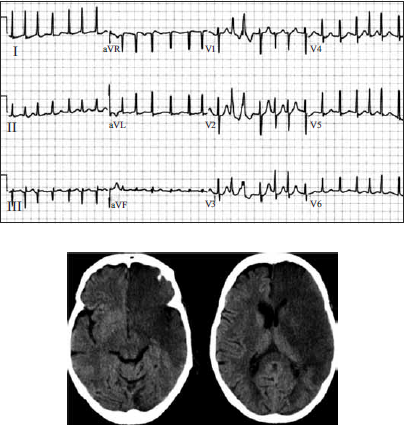

Mulher, 63 anos, foi admitida no pronto-atendimento após ser encontrada pelos familiares, caída, em casa. Ao exame físico, apresentava rebaixamento do nível de consciência (Glasgow = 11), ausculta cardíaca irregular e desvio conjugado do olhar para a esquerda. O eletrocardiograma e a tomografia computadorizada de crânio encontram-se ilustrados a seguir.

Das medidas apresentadas, assinale aquela que pode ser deletéria ao caso em questão e, portanto, deverá ser evitada inicialmente, mesmo diante de uma indicação precisa.